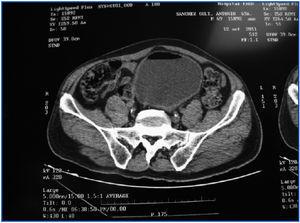

La pielo-TAC (tomografía axial computarizada específica) mostró aire en el lumen vesical hacia su cara ventral.

La cistitis enfisematosa fue descubierta por Eisenlohr1 a fines del siglo XIX, y Bailey2 caracterizó esta enfermedad. Puede presentarse desde una forma asintomática hasta sepsis severa, pasando por cuadros de neumaturia y abdomen agudo. En nuestro caso, el síntoma cardinal fue neumaturia y la presencia de aire en la vejiga, demostrada por TAC (figura 1).

Figura 1. Pielo-TAC que muestra aire intravesical